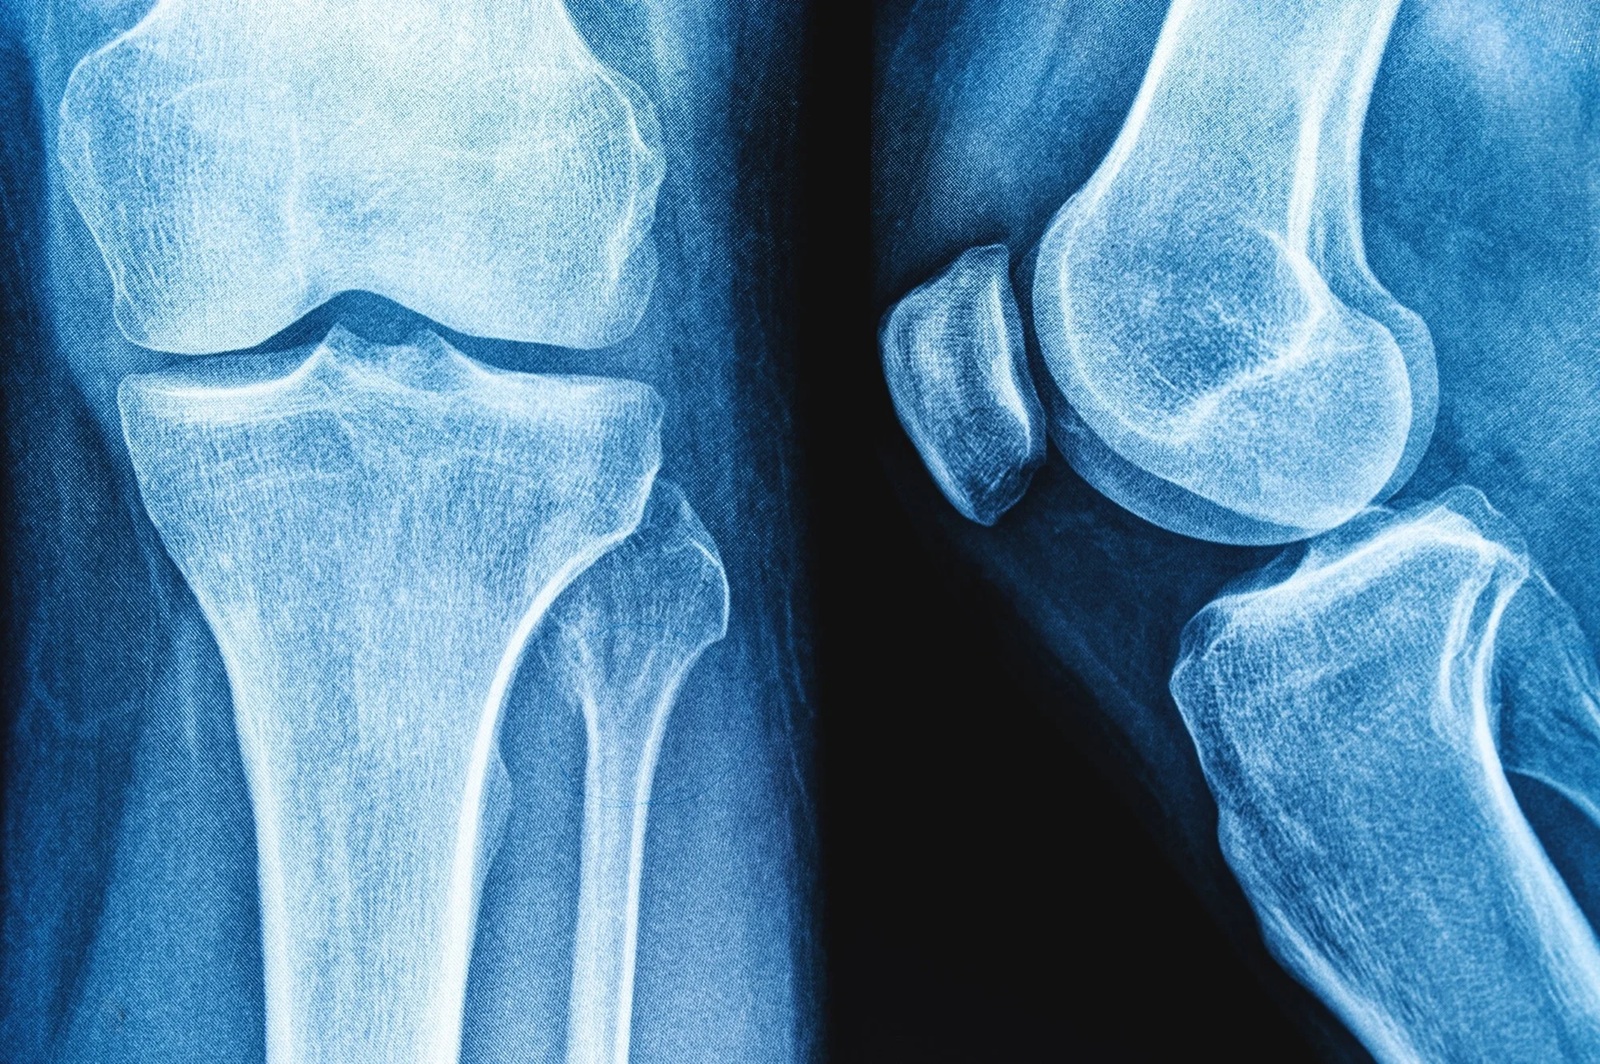

در دوران بزرگسالی، تشکیل استخوان کندتر و تجزیهی استخوان سریعتر میشود که در نهایت میتواند منجر به کاهش تودهی استخوانی و افزایش خطر شکستگیهای ناشی از شکنندگی شود. کلسیم، ویتامین D و فسفر برای سلامت و عملکرد استخوانها ضروری هستند. ماست منبع خوبی از پروتئین، پتاسیم، کلسیم، ویتامینها، روی و سلنیوم است؛ عناصری که همگی در تقویت و رشد استخوان نقش دارند.

به شکل خاص، یک مطالعه نشان داد مصرف مکرر ماست با کاهش خطر پوکی استخوان در استخوان زند زبرین (Radius) همراه است و مطالعهای دیگر نشان داد زنانی که بیشترین مصرف ماست را داشتند، تراکم استخوان گردن فمور و مفصل ران بیشتری نسبت به گروه با کمترین مصرف داشتند. همچنین یک مطالعه دیگر ارتباطی ضعیف بین مصرف ماست و کاهش خطر شکستگی لگن یافت.

در فراتحلیلها، هیچ ارتباط معنیداری بین مصرف ماست و خطر شکستگی لگن در سطوح گزارششدهی مصرف مشاهده نشد. با این حال، مصرف ماست اثر مثبت ولی بسیار ناچیزی بر تراکم استخوان فمور داشت (SMD ≈ ۰.۰۰۹)، که از دید بالینی بیاهمیت تلقی میشود و نشان میدهد اثر آن بر سلامت اسکلت حداقلی است.